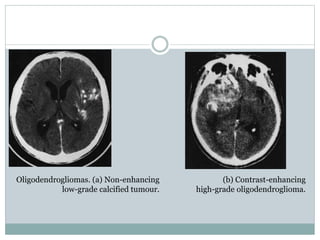

Oligodendrogliomas. (a) Non-enhancing

low-grade calcified tumour.

(b) Contrast-enhancing

high-grade oligodendroglioma.

Radiological investigation

CT scanning and MRI are the fundamental

investigations.

They will confirm the diagnosis of an

intracranial tumour and in many cases the diagnosis

of oligodendroglioma will be highly probable.

Calcification will be present in 90% of cases

and over half show contrast enhancement (Fig.

6.11.)